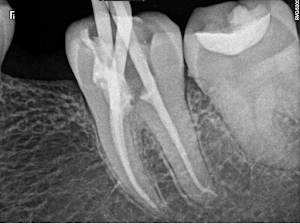

Welcome to our gallery

See how our company transforms ideas into reality. This gallery is a visual testament to our work and achievements.